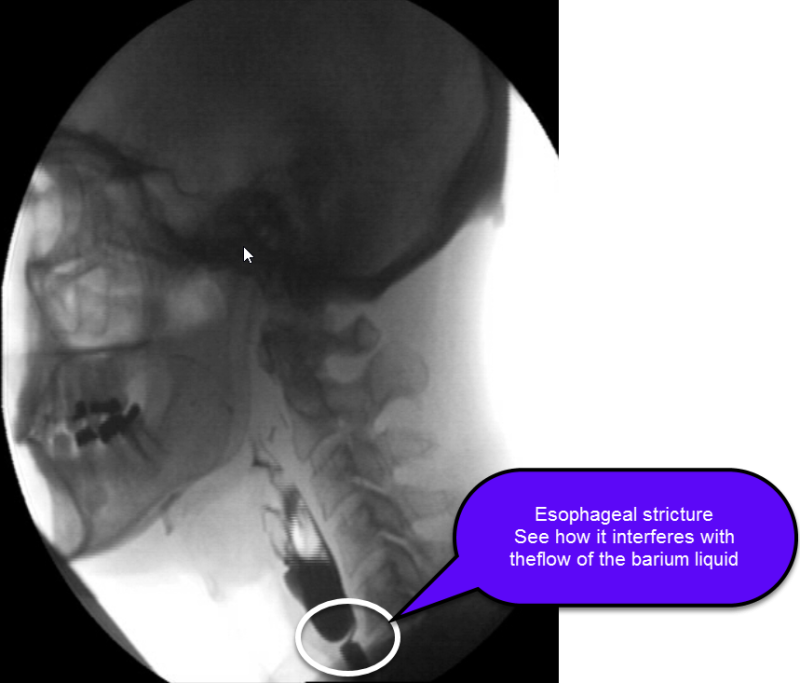

Barium xray of a benign esophageal stricture. Download Scientific What Is Esophageal Stricture The esophagus is a muscular tube that connects the mouth to the stomach and is the conduit for food bolus to pass from the throat to the. Web an esophageal stricture is a narrowing of the esophagus that makes swallowing difficult. It can be caused by gerd, infections,. It often presents with difficulty swallowing and has many potential etiologies. Web. What Is Esophageal Stricture.